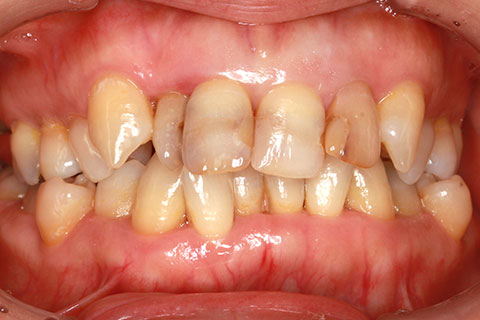

オールセラミックの症例2

- 年齢・性別

- 45歳男性

- 治療期間

- 2ヶ月

- 抜歯

- なし

- 治療費

- 70.4万円

- 備考

- 前歯8本の歯列不正によるセラミック治療

- 治療内容

- 歯質を削除し、セラミック冠をセメント合着

- 施術の副作用(リスク)

- 知覚過敏、歯髄炎、荷重負担